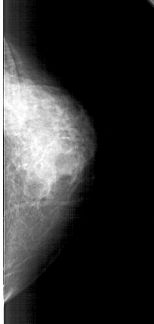

A_1475_1.LEFT_CC

LEFT_CC LINES 4246 PIXELS_PER_LINE 1921 BITS_PER_PIXEL 12 RESOLUTION 43.5 OVERLAY

FILE: A_1475_1.LEFT_CC.OVERLAY

TOTAL_ABNORMALITIES 1

ABNORMALITY 1

LESION_TYPE CALCIFICATION TYPE AMORPHOUS DISTRIBUTION CLUSTERED

ASSESSMENT 4

SUBTLETY 3

PATHOLOGY BENIGN

TOTAL_OUTLINES 1

BOUNDARY